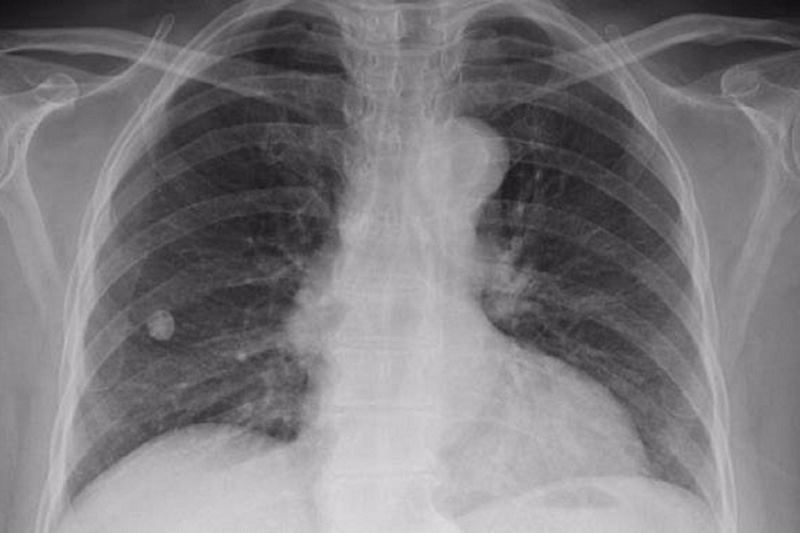

رئیس شبکه بهداشت زاهدان به مناسبت ۲۳مهر روزملی مبارزه با سل گفت: شیوع سل در سیستان و بلوچستان بالاتر از میانگین کشوری است.

او افزود: درحالی که میانگین متوسط ابتلا به سل در کشور به ازای هر ۱۰۰ هزار نفر جمعیت ۱۱نفر است اما این آمار در استان ۲۰ نفر در ۱۰۰ هزار نفر است.

رئیس شبکه بهداشت زاهدان اظهار کرد: آمار سیستان و بلوچستان در خصوص ابتلا به سل با توجه به وجود ریزگردها در بیشتر ایام سال بخصوص در شمال استان دو برابر آمار کشوری است.

راشدی گفت: در ۶ ماهه اول سال جاری ۷۲بیمار سل مثبت داشته ایم که نسبت به سال قبل افزایش داشته است.

او ادامه داد: بیشترین مشکل ما در مقابل این بیماری، سل مقاوم به درمان است که متاسفانه خطرناک هم است و قابلیت سرایت به سایر افراد را هم دارد.

رئیس شبکه بهداشت زاهدان تصریح کرد: از جمله علائم این بیماری می توانیم به سرفه های بیشتر از دوهفته تب شبانه و کاهش وزن و کم خونی اشاره کرد.

او در پایان خاطرنشان کرد: بیماری سل بیماری تنفسی است که قابلیت انتقال از فردی به فرد دیگری را دارد.»